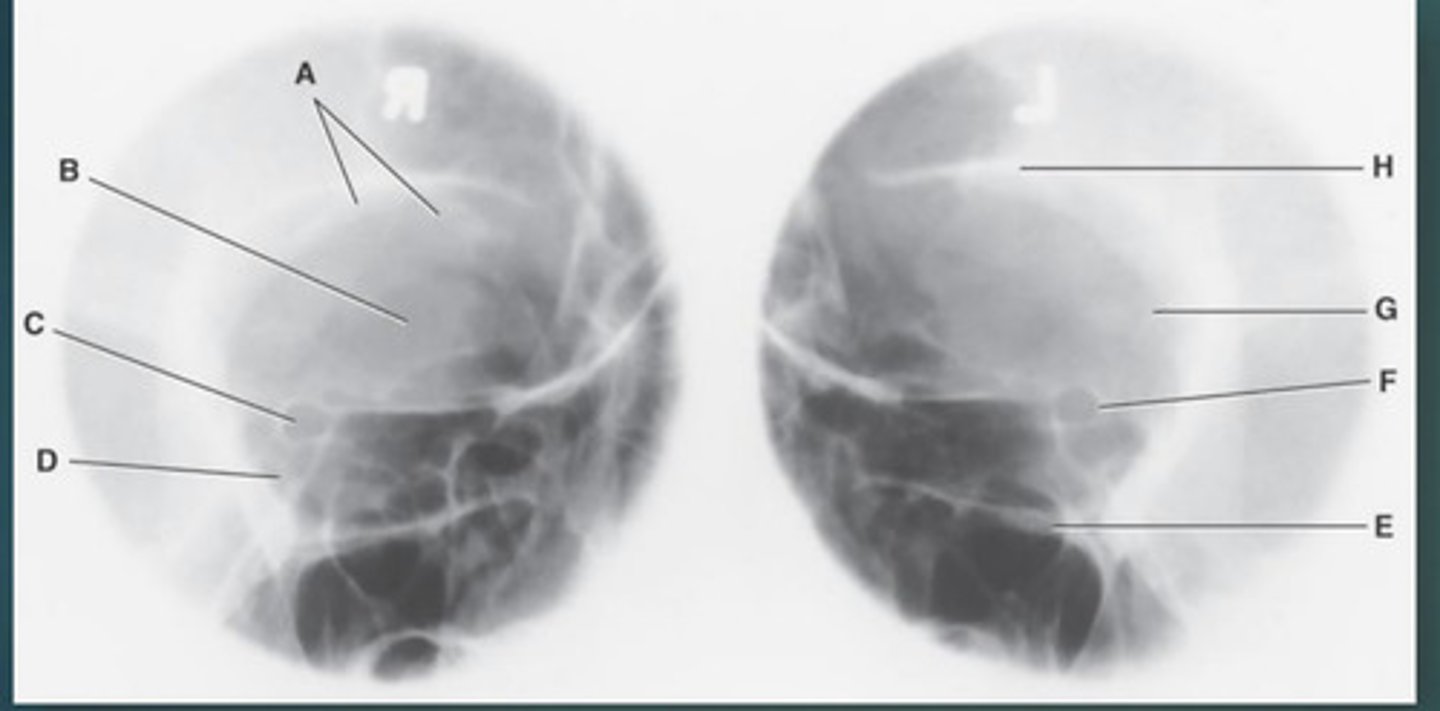

Lateral sinus

What position?

L. Orbital roofs

A.

L. Greater wings of sphenoid

B.

sella turcica of sphenoid

C.

L. Sphenoid sinus

D.

L. Rami of mandible

E.

L. Maxillary sinuses

F.

L. Ethmoid sinuses

G.

L. Frontal sinuses of frontal bone

H.